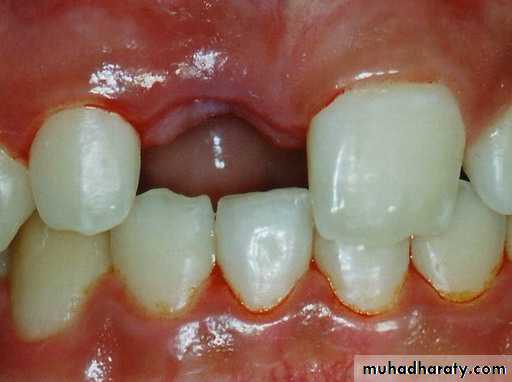

• Preservation of bone: reduce bone loss and gum recession associated with missing teeth• loss of teeth →

• Lack of stimulation to the residual bone →

• Decrease in bone density, height and width.

Bone resorption after extraction

Bone resorption in edentulous patientsMost of the bone loss occurs in the first year after extraction) 2mm per a year).

Continued bone loss for more than twenty years 0.2 mm per a year.

Four fold greater in mandible than in maxilla.

Upwards and medially in maxilla, downwards and laterally in mandible.

• Teeth stimulate bone → maintain bone.

• Implants stimulate bone → maintain bone.

• Complete and partial dentures don’t stimulate bone →

• Bone resorption, acceleration of bone resorption if ill fitting →

• Decreases the surface area available for prosthesis support.

• Eliminates favourable anatomy for retention.

• Results in unfavourable denture bearing areas.